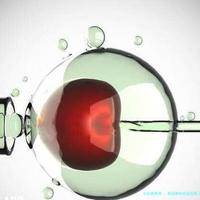

取尽卵随后,男性一方也需要配合取精,然后实验室里把精子和卵子结合,培育成胚胎。这时候医生会决断是直接移植,要么先把胚胎冷冻起来,等体质好了再移植。要是是直接移植,那卵泡取出后大概3~五日就能安排胚胎移植;如果是冻存胚胎,那就要等接下来的周期或者调理好身体后再来。